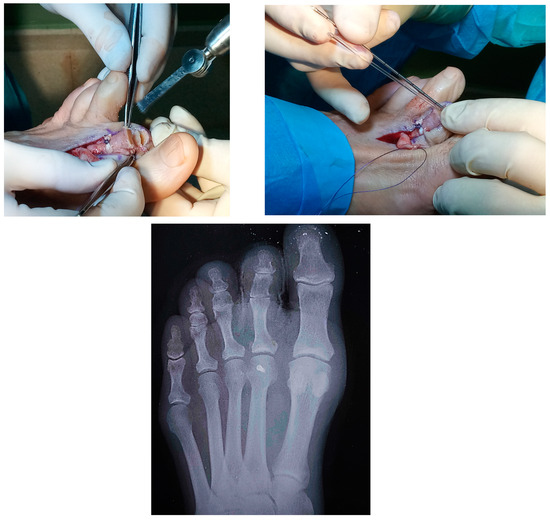

2.1. Case 1

2.2. Case 2